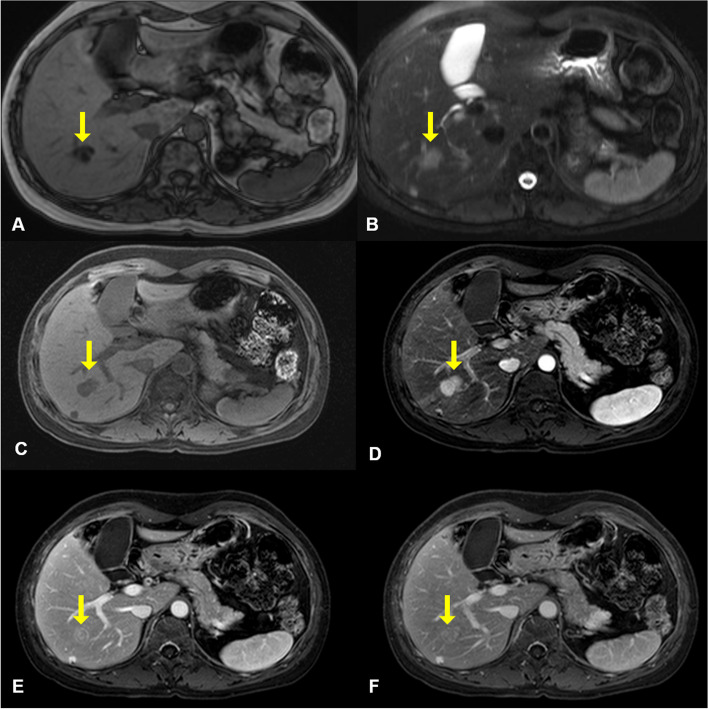

A 49-year-old woman was referred to our institution with a liver mass of 3 cm diameter that was incidentally identified on abdominal computed tomography during a medical check-up. She had been diagnosed with bilateral breast cancer at the age of 30, when she underwent bilateral modified mastectomy. Abdominal MRI revealed two masses in both the liver and pancreas. The mass in the right hepatic lobe (segment 6) demonstrated low signal intensity on T1‑weighted images (Fig. 1A) and intermediate signal intensity on T2‑weighted images (Fig. 1B), and was difficult to differentiate from hepatocellular carcinoma. Dynamic gadoxetic acid-enhanced MRI of the liver mass showed intense enhancement on the arterial phase image, and equivocal washout of the tumor on the portal phase and delayed phase images (Fig. 1C–F). In the pancreatic tail, a subtle high signal intensity lesion was identified on T2‑weighted images (Fig. 2A). Dynamic gadoxetic acid-enhanced MRI of the pancreatic mass showed low signal intensity on the pre-contrast image and low contrast enhancement on the arterial phase image, followed by delayed contrast enhancement on portal phase and delayed phage images (Fig. 2B–E).

Fig. 1.

Abdominal magnetic resonance images of the liver mass. The mass in the right hepatic lobe demonstrated low signal intensity on T1‑weighted images (A) and intermediate signal intensity on T2‑weighted images (B). Dynamic gadoxetic acid-enhanced magnetic resonance images of the liver mass showed low signal intensity on pre-contrast image (C), intense enhancement on the arterial phase image (D), and equivocal washout of the tumor on portal phase (E) and delayed phase (F) images. The yellow arrow indicates the mass